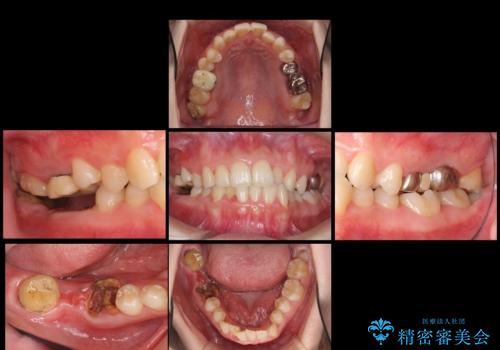

- 奥歯が虫歯で他院で抜かないといけないといわれ来院。

虫歯を放置していたが、これを機にしっかり通って治したいとのことでした。

右下は虫歯がひどく、抜歯が必要でした。また、右下の一番奥の歯は親知らずのため使うことができない状態でした。

右上に部分矯正を行い、クリアランスを確保した後、右下にイプラントを2本埋入しています。